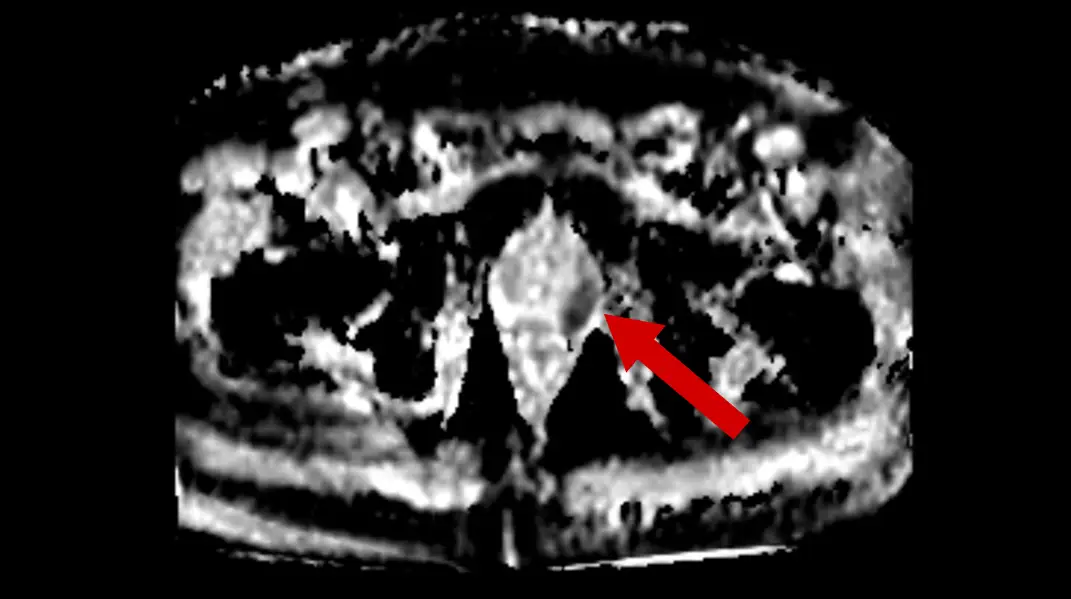

Axial T2 sequence shows the darker lesion in the left peripheral zone (red arrow) compared to the normal increased T2 signal in the contralateral peripheral zone.